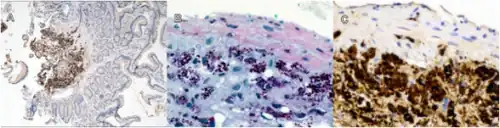

Tropheryma whipplei is a bacterium that is the causative organism of Whipple's disease, and rarely, endocarditis.[2]

While T. whipplei is categorized with the Gram-positive Actinomycetota, the organism is commonly found to be Gram-positive or Gram-indeterminate when stained in the laboratory.[2] Whipple himself probably observed the organisms as rod-shaped structures with silver stain in his original case.[4]

Individuals who are most susceptible to Whipple's disease are those with decreased ability to perform intracellular degradation of ingested pathogens or particles, particularly within macrophages. Several studies indicate that defective T-lymphocyte function may be an important predisposing factor for the disease.[10]